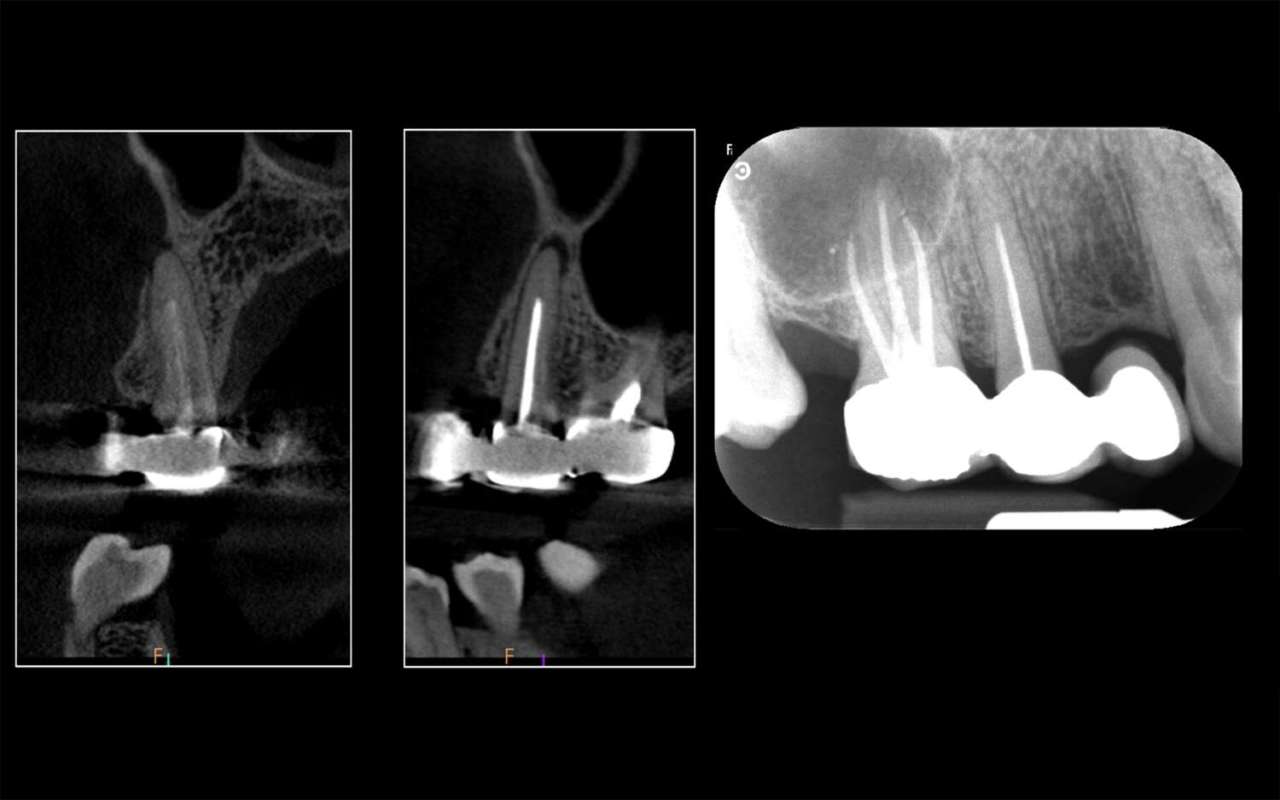

All’esame 2D, è possibile notare che l’elemento 1.5 presenta una terapia canalare incongrua (Figura 1). Sebbene l’apice radicolare non risulti associato a una lesione periapicale, il paziente riferisce dolore sia alla percussione sia alla palpazione nella zona. Consapevoli dei limiti dell’esame 2D, decidiamo di procedere alla valutazione 3D.

La CBCT eseguita con FOV ridotto e alta risoluzione (Figura 1) evidenzia una lesione periapicale di piccole dimensioni con erosione, a livello apicale, della corticale vestibolare. Inoltre, l’esame 3D consente di notare una completa ostruzione del lume canalare nel terzo apicale, provocata da calcificazioni. Si tratta di calcificazioni severe che occludono completamente lo spazio endodontico.